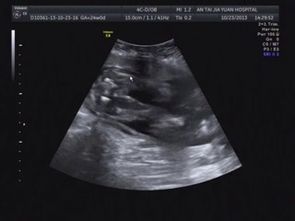

脾臟B超、肝臟和腎臟B超檢查前:一般無(wú)須特別準(zhǔn)備,但最好是空腹進(jìn)行。病人如同時(shí)要作胃腸、膽道X線造影時(shí),超聲波檢查應(yīng)在X線造影前進(jìn)行,或在上述造影3天后進(jìn)行。

指導(dǎo)意見(jiàn): 如需用區(qū)別病變是否在盆腔,檢查前要保持膀胱充盈。作腹腔器官檢查時(shí),遇腹腔氣體過(guò)多或有便秘的患者,醫(yī)生可能囑檢查前日晚服緩瀉藥,或在檢查前灌腸,患者應(yīng)當(dāng)認(rèn)真配合。

如檢查盆腔的子宮及其附件、膀胱、前列腺等臟器時(shí),檢查前需保留膀胱尿液,可在檢查前2小時(shí)飲開(kāi)水1000毫升左右,檢查前2-4小時(shí)不要小便。